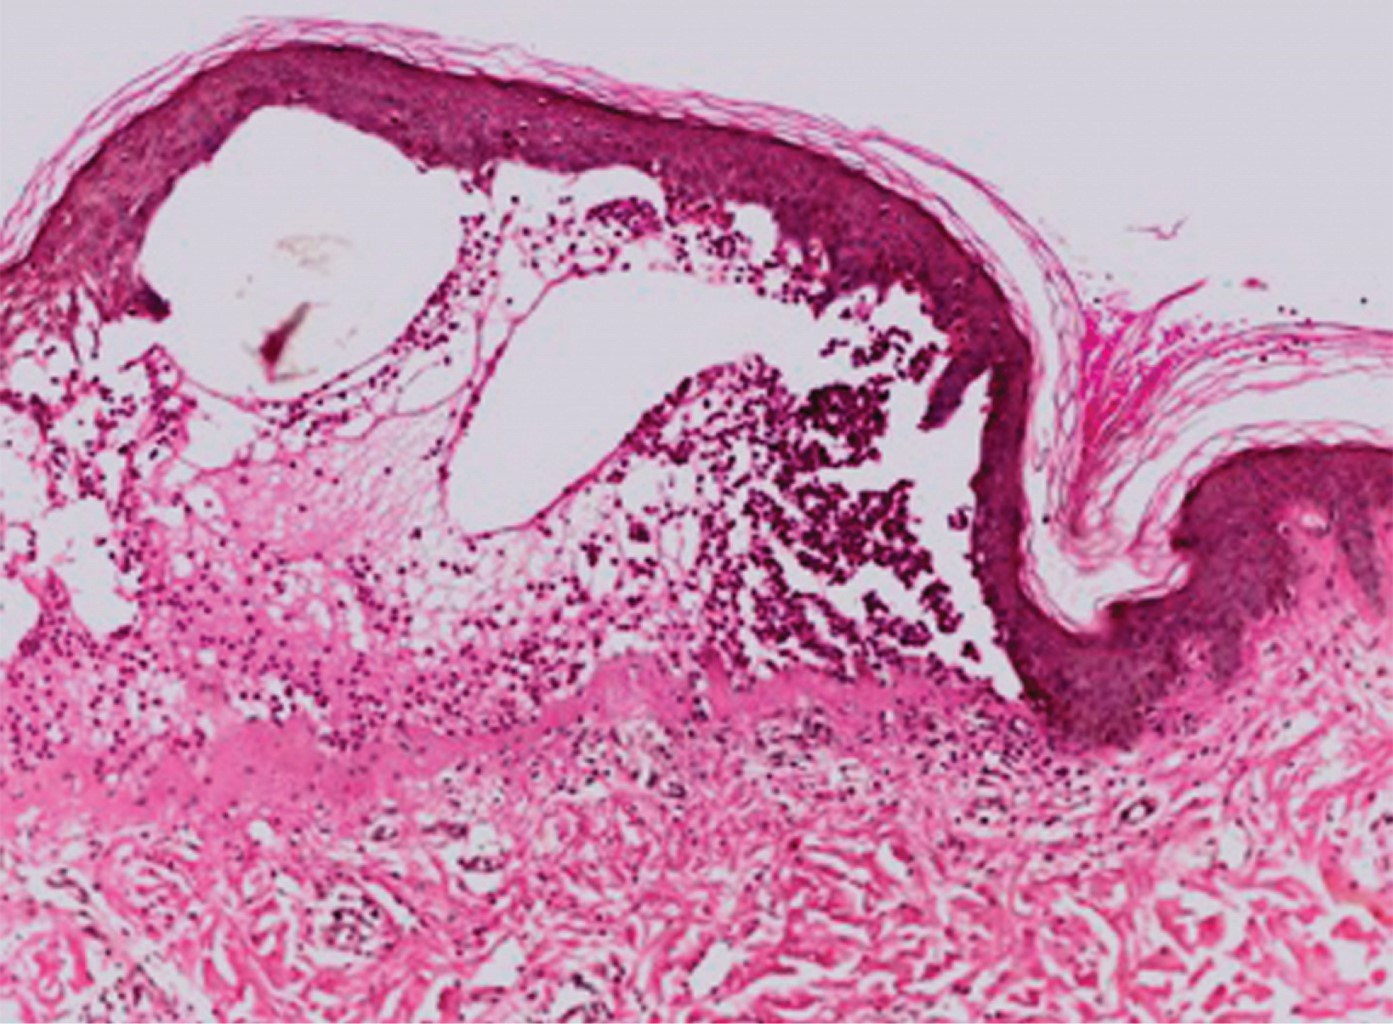

Se realiza biopsia de una de las vesículas, y con tinción de rutina se observó una ampolla subepidérmica (Figura 3) con restos de fibrina en el interior y presencia de polimorfonucleares (Figura 4), por lo que se solicita inmunofluorescencia e inmunohistoquímica para IgA e IgG (Figura 5), las cuales fueron reportadas como positivas, concluyendo que se trata de una enfermedad por IgA lineal.

Figura 4